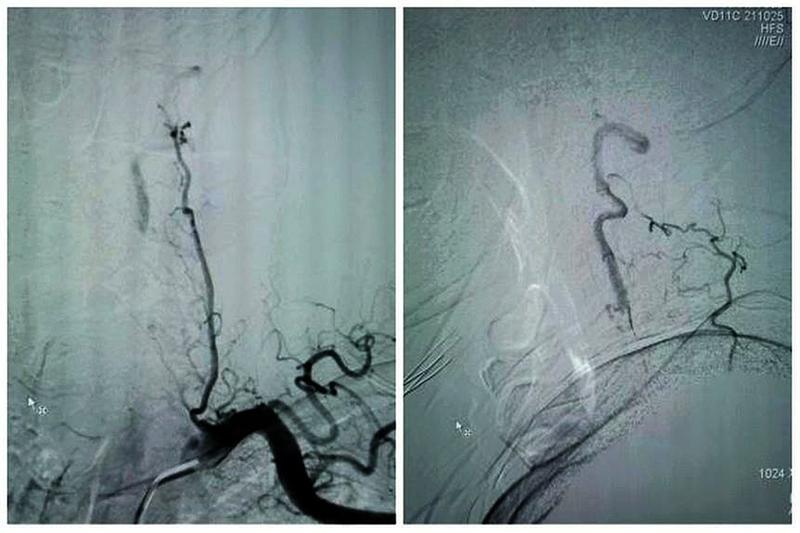

患者拜某,男,65岁,因反复头晕、晕厥1年,加重10天入院,既往5年前因心肌梗死在外院冠脉植入5枚支架。本次发病后当地医院发现患者脑后部的主干动脉——双侧椎动脉在颈部完全闭塞,当地医院药物医治无效,患者慕名从商洛来到我院神经内科。入院后经过脑血管造影发现患者双侧椎动脉颈部闭塞段大约10cm,闭塞远端经过甲状颈干及肋颈干向V2近颅底以远代偿供血,但因代偿不足,患者近来反复脑梗死2次,此次入院再次提示小脑新鲜脑梗死。

最终,在患者入院第4天,张桂莲教授带领的介入团队选择局麻条件下为患者成功实施了神经介入领域的高难度手术—左侧无残端椎动脉长节段慢性闭塞再通术。因术前清晰的影像显影及准确的体外定位标记,左侧优势椎动脉顺利开通,手术耗时仅仅约90分钟。术中及术后患者配合良好,无任何不适。出院前复查头颈一体化超声提示左侧椎动脉支架位置良好,血流通畅,颅内血流速度及频谱未见明显异常。充分向患者及家属告知出院注意事项及复查时间后,目前该患者已顺利出院。